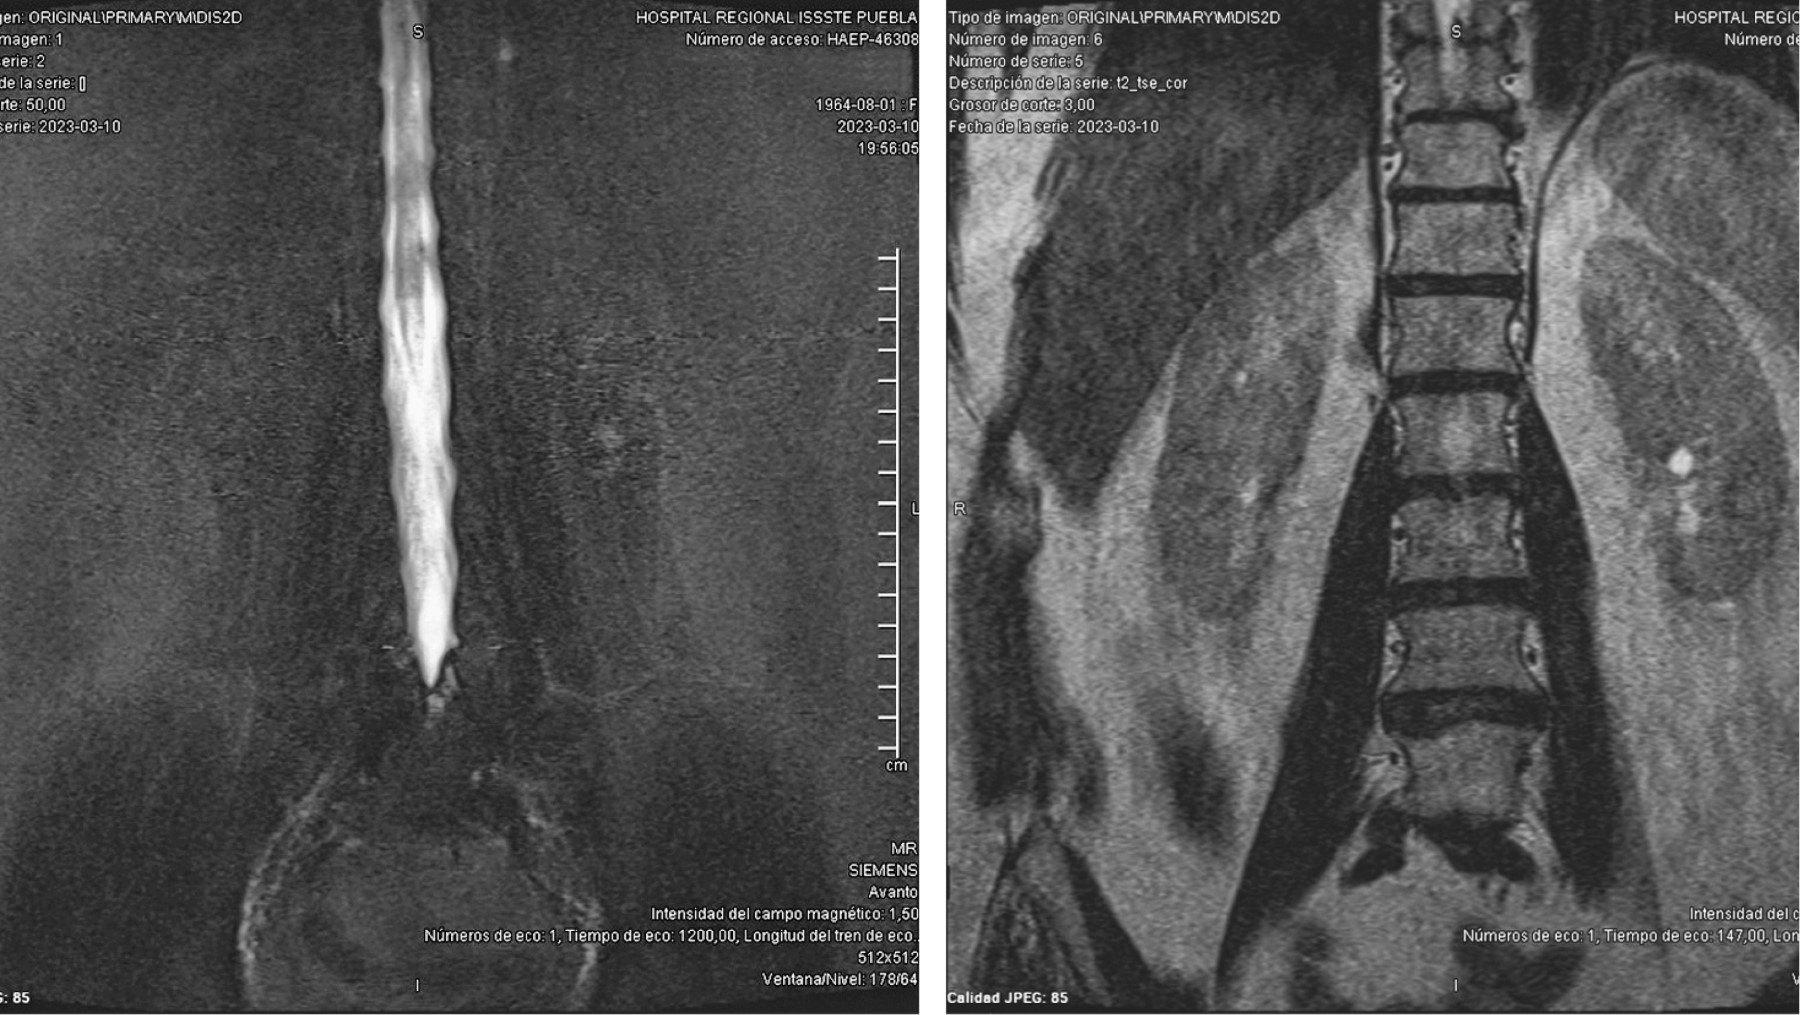

Ozone is a medical gas described since the 19th century; the ozone therapy has evolved to date in terms of its applications and its usefulness in various diseases due to its action at the molecular level and in dissimilar diseases associated with painful processes of inflammatory origin such as present in herniated discs of the spine, although the benefits of its application are currently in controversy, as well as the various complications that may occur after its application. Pneumocephalus is a complication that occurs in the background of a head injury or neurosurgery. Ozone infiltrations are used for the treatment of disc prolapse to reduce clinical symptoms. The anti-inflammatory effect of ozone is supported by its ability to oxidize compounds that contain double bonds such as arachidonic acid and prostaglandins, which are active substances with high concentrations in the inflammatory process. The appearance of pneumoencephalus and arachnoiditis chemical after epidural injection and also with ozone infiltrations is a rare complication but it has been described in recent years as a devastating post-application complication. Arachnoiditis can present as sensory and motor deficits, paresthesias, transient radicular neurological syndrome (TRNS), cauda equina syndrome, and conus medullaris. In relation to arachnoiditis, cases as severe as cauda equina syndrome after spinal anaesthesia, and more benign such as TSNR have been described, characterized by low back pain that radiates to the lower extremities, and not associated with motor deficits. neither sensitive, nor sphincter incontinence, which appears in the first 24 hours, which can last several days, and which resolves without neurological sequelae. Understanding the pathophysiology is important to assess and diagnose this type of neurological complications, especially in patients with disc disease who have undergone this type of treatment. The purpose of this report is to present the case of a patient with disc disease with the presence of radiculopathy who underwent infiltration by ozone therapy, who immediately presented complications such as pneumoencephalus and chemical arachnoiditis that led her to remain hospitalized in intensive care and present cauda equina syndrome.REFERENCES